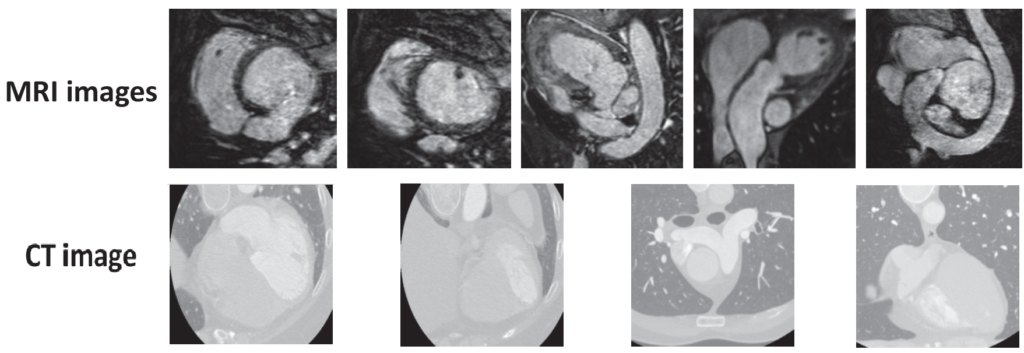

MRI와 CT에 대해선 다들 병원 등에서 들어 보셨을 것이라 생각이 드는데요, 본 논문에서 사용한 데이터셋은 아래처럼 생겼다고 합니다.

위 모델의 각 모달 사진을 보시면 서로 다른 곳이 촬영된 이미지인것을 볼 수 있습니다. 실제로 본 논문에서 실험에 사용한 dataset의 경우도 MRI-CT가 unpair한 이미지라고 합니다.